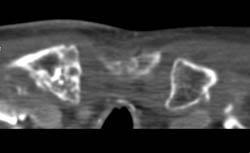

DIEP Flap Planning